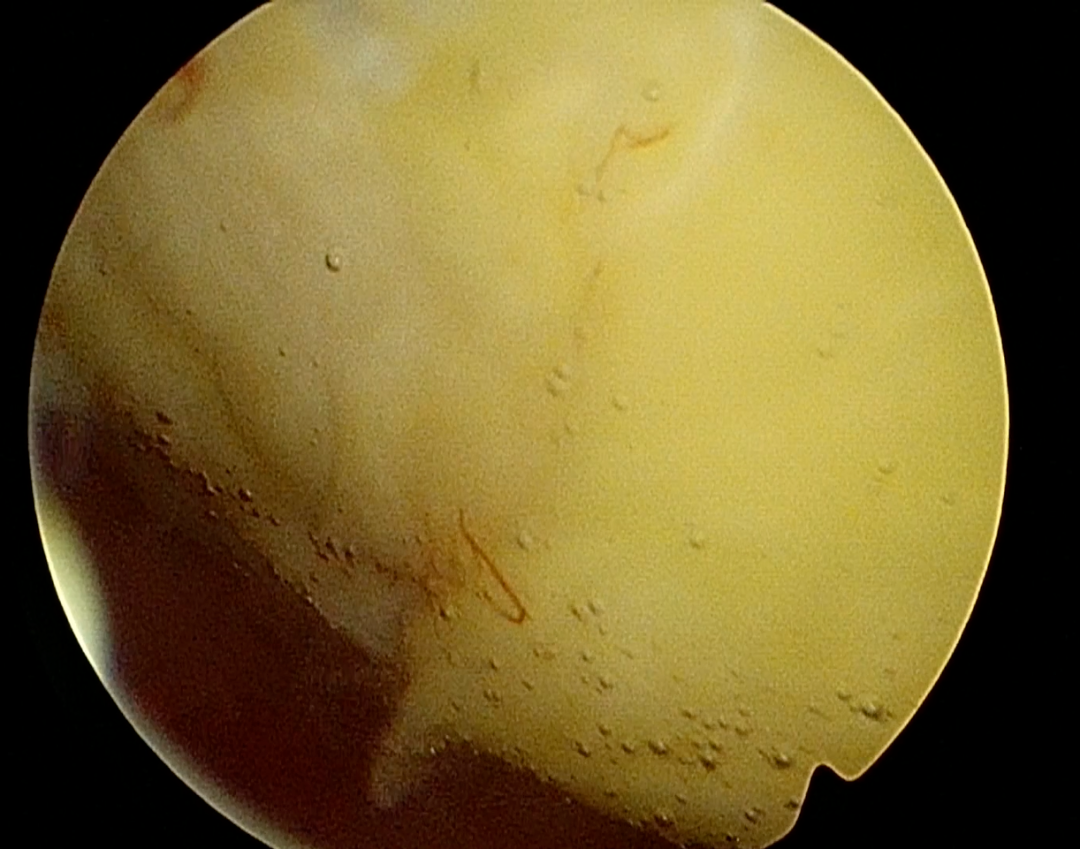

夏教授为患者安排了三维超声和宫腔镜检查,结果显示肌瘤位于宫底后壁,2-5型贯穿整个肌层,直径95mm,周边血流丰富。如果选择腹腔镜手术剔除肌瘤,子宫肌层完整性受到破坏,存在瘢痕子宫妊娠子宫破裂风险,宫腔镜手术创伤更小恢复更快,患者有生育计划,如果能通过宫腔镜手术治疗,是对生育功能最大的保护。但巨大的肌瘤马上手术,风险太大。夏教授决定先予GnRH-a类药物治疗手术预处理,缩小肌瘤体积,改善贫血后择期手术。4个月治疗后,血色素正常,宫腔镜检查显示肌瘤继续向宫腔突入,但仅稍微缩小至直径88mm,这对于宫腔镜手术仍然是个挑战。从“手术安全是第一位”的角度出发,夏恩兰主任和彭雪冰主任决定腹腔镜监护下进行宫腔镜手术,根据术中情况随时调整手术方式,“进可攻,退可守”。

6ce1d466917240c0d97ee2d72455cfab.jpg

术中见肌瘤突向并充满了宫腔,手术初始,宫腔可操作的空间十分有限,彭主任用娴熟的宫腔镜手术技术迅速高效切除缩小肌瘤。这一过程需要面临出血、灌流介质过度吸收综合征、子宫穿孔等重重风险。麻醉医师龚璠在手术过程中,密切关注患者生命体征为手术保驾护航。终于,在不懈的努力下,完全切除了这一巨大肌瘤,去除了导致患者大出血的元凶,也守卫了“生命宫殿”,为患者保留了生育的希望。术后患者恢复良好,顺利出院。